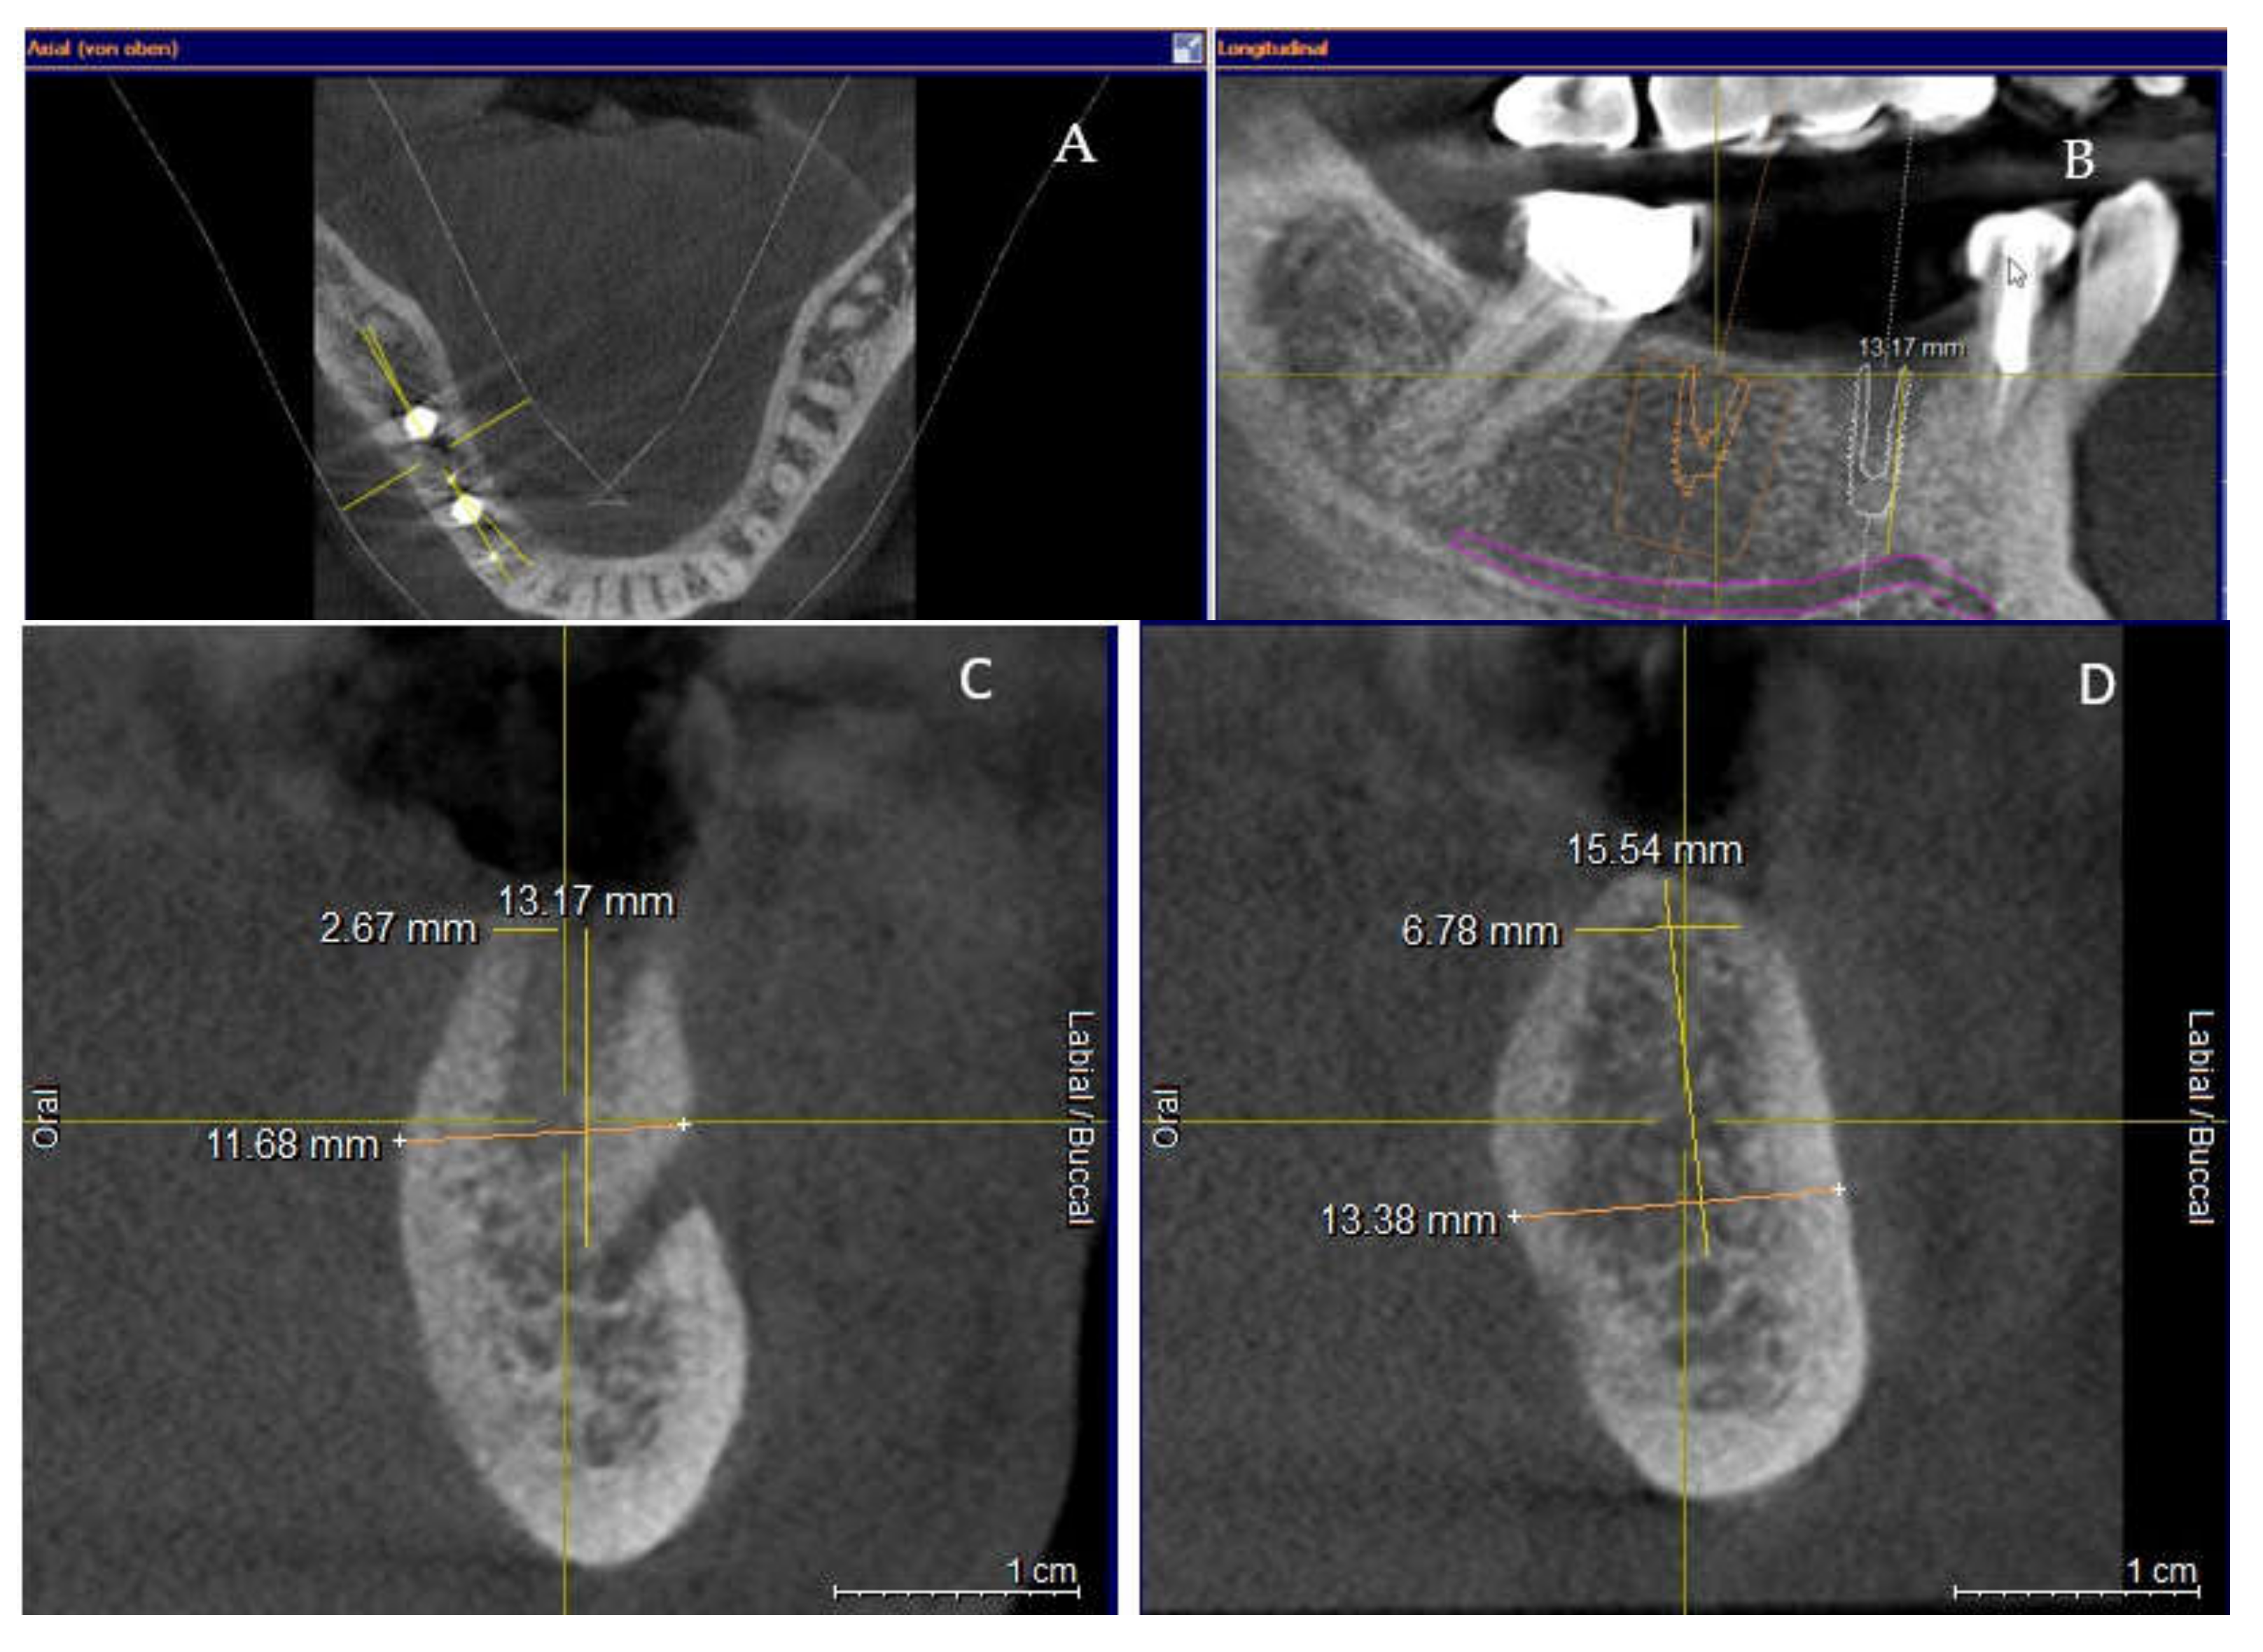

Clinical and CBCT aspects of patient from the test group, describing the stages of S-GBR technique and implant-prosthetic stage, are presented in Figure 1, Figure 2, Figure 3, Figure 4, Figure 5, Figure 6, Figure 7, Figure 8, Figure 9, Figure 10 and Figure 11. CBCT exam allows the evaluation of the horizontal alveolar bone defect and the position of the mandibular alveolar nerf (Figure 1A,B). Figure 1C,D show cross-sectional CBCT aspects of the implant sites. Figure 2 shows the narrowed mandibular alveolar bone with horizontal resorption. Figure 3 shows the exposed buccal surface of the alveolar ridge with severe horizontal resorption, after flap opening. The inserted implants (4.5 mm diameter, 11.5 mm length) and osteosynthesis screws (45° from the occlusal plan) are shown in Figure 4A. The placement of graft (autologous bone and xenograft) and collagen membrane is shown in Figure 4B. Figure 5A shows tension-free sutures, due to periosteal incisions alveolar ridge. Figure 5B shows clinical aspect at 7 months after surgery, with gingival tissue adherent on the reconstructed alveolar ridge. Figure 6 shows OPG aspect at follow-up of 7 months, with osseointegration of the dental implants. Figure 7A shows clinical aspect before osteosynthesis screws removal. Figure 7B shows clinical aspect after osteosynthesis screws removal. Figure 8A shows healthy peri-implant soft tissues. Figure 8B shows repositioning key for perfect position of abutments. Figure 10A,B show clinical aspects of implant-supported prosthetic restoration. Figure 11A,B show CBCT aspects of Osseo integrated dental implants at 24 months follow-up.

Figure 1.

(A,B) Pre-operative CBCT aspects. (A) Narrow residual alveolar ridge. (B) Analysis of the mandibular nerve position. (C,D) Pre-operative CBCT aspects (cross-sectional).